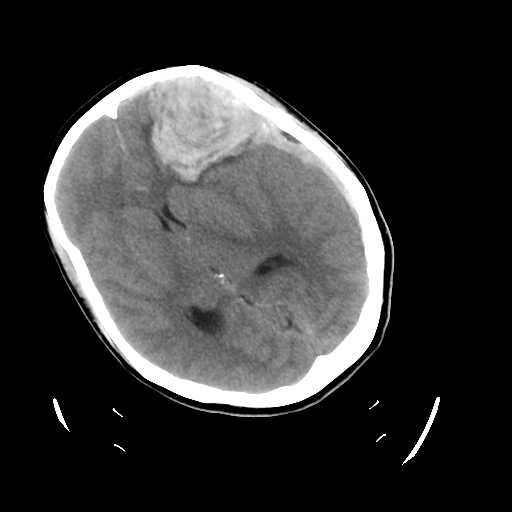

在接诊后,急诊科医师迅速启动绿色通道,头部CT检查显示脑出血,且出血量较大,中线明显移位,随即联系医院神经外科会诊。

左侧额叶及硬膜下血肿(术前)

额叶血肿清除术后,中线基本居中